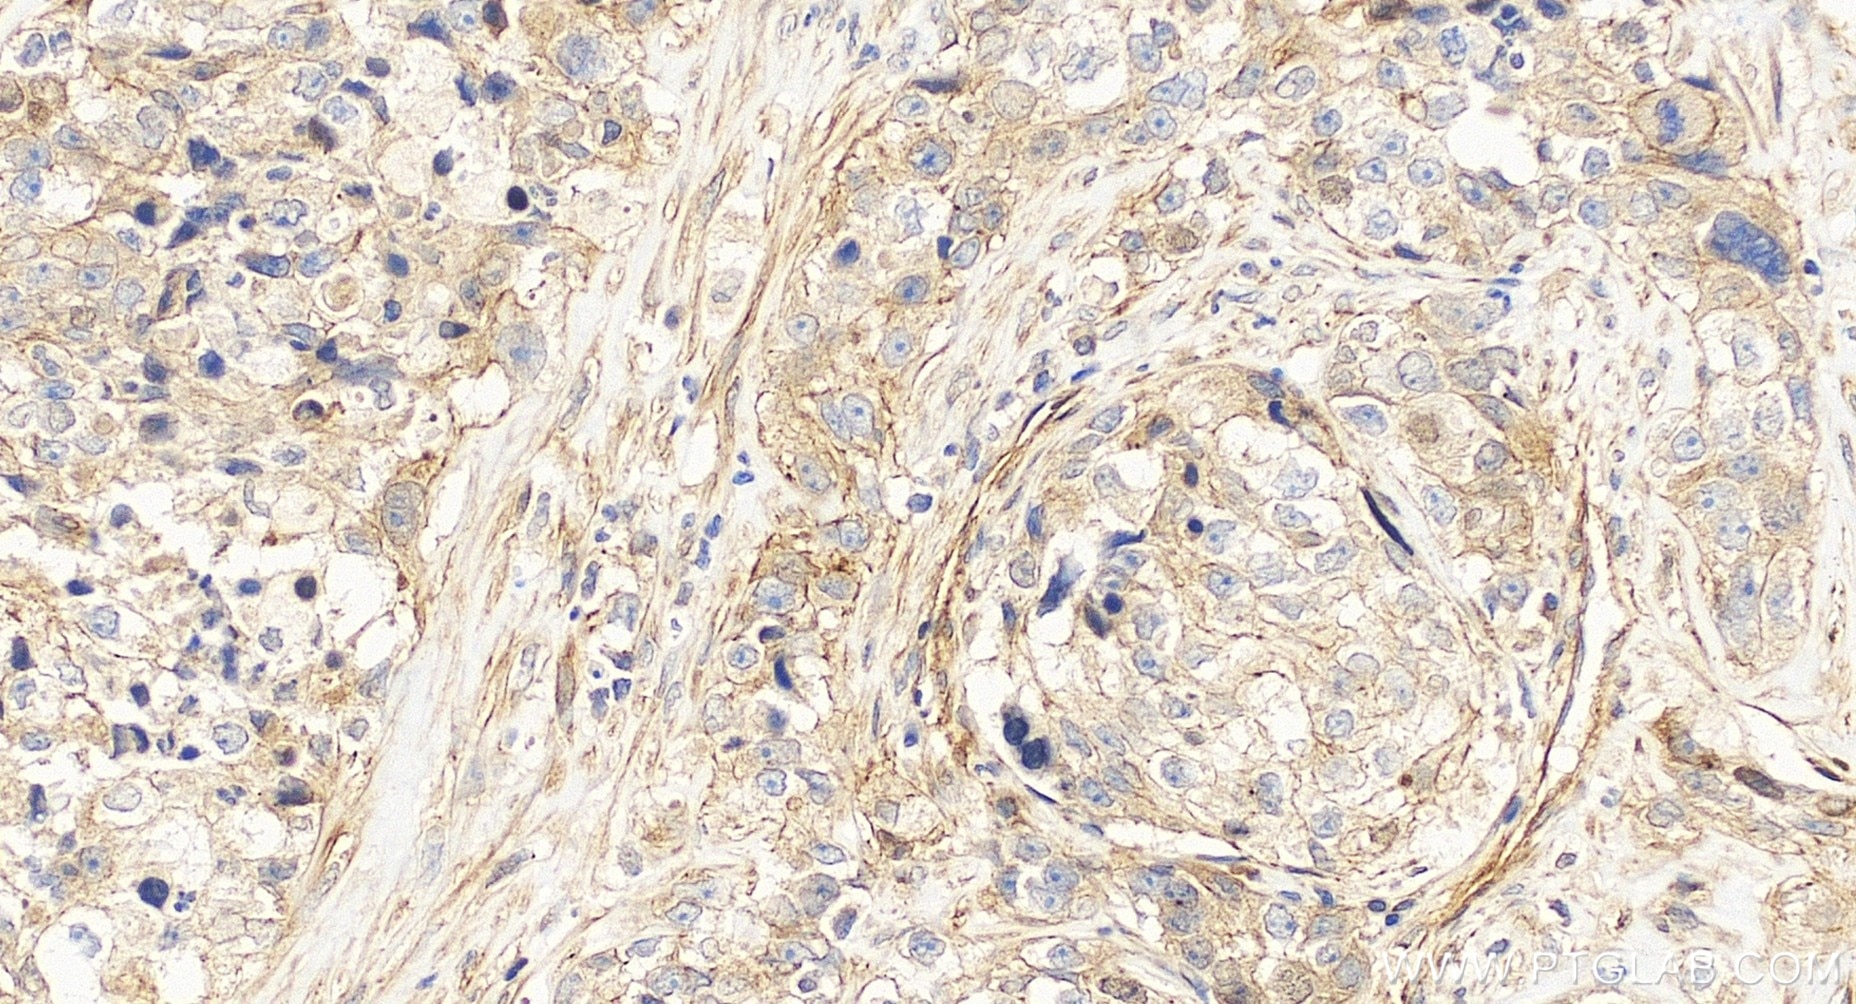

| Positive IHC detected in | human ovary cancer tissue Note: suggested antigen retrieval with TE buffer pH 9.0; (*) Alternatively, antigen retrieval may be performed with citrate buffer pH 6.0 |

| Immunohistochemistry (IHC) | IHC : 1:50-1:500 |

CUE domain-containing 2 (CUEDC2) is a ubiquitin-binding motif-containing protein involved in the regulation of the cell cycle, inflammation, and tumorigenesis. It is ubiquitously expressed in human tissues and organs, not only highly expressed in the normal brain, heart and testis, but also some kinds of cancers, such as breast, ovarian and kidney cancers. CUEDC2 could act as an adaptor protein to target IκB kinase (IKK) for dephosphorylation and inactivation by recruiting protein phosphatase (PP1), and thus repressed activation of the transcription factor NF-κB. Moreover, CUEDC2, is a key factor in endocrine resistance in breast cancer.